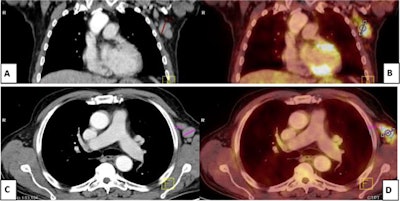

A 54-year-old male patient with Hodgkin's lymphoma treated with rituximab four months prior to vaccination. (A) Coronal and (C) axial contrast-enhanced CT images revealed multiple enlarged left axillary lymph nodes. (B) Coronal and (D) axial F-18 FDG-PET/CT images revealed enlarged and FDG-avid left axillary lymph nodes. At first, this was diagnosed as progression. Ultrasound-guided biopsy-revealed reactive follicular hyperplasia with no malignancy. Clinical history revealed that the patient received a second dose of the Pfizer-BioNTech COVID-19 vaccine in his left arm seven days before the PET/CT scan. Image courtesy of the Egyptian Journal of Radiology and Nuclear Medicine through CC BY 4.0.In this study, the authors sought to explore the issue further by investigating the incidence of VAHL in patients undergoing rituximab treatment for lymphoma who received second doses of the Pfizer-BioNTech vaccine.